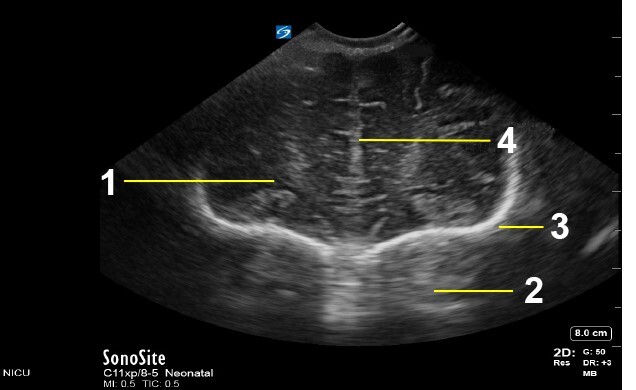

Neonatology C1 Image

Frontal Lobe

Orbit

Skull

Interhemispheric Fissure